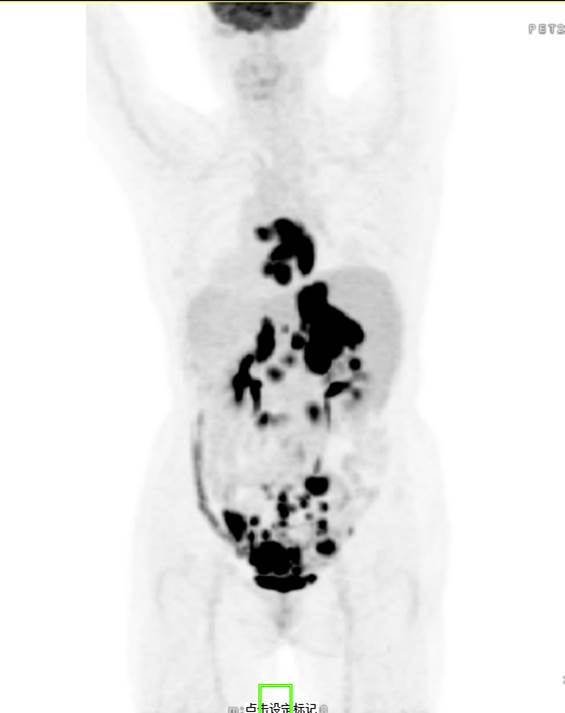

PET/CT影像圖

左/右心房病灶放射性攝取明顯增高